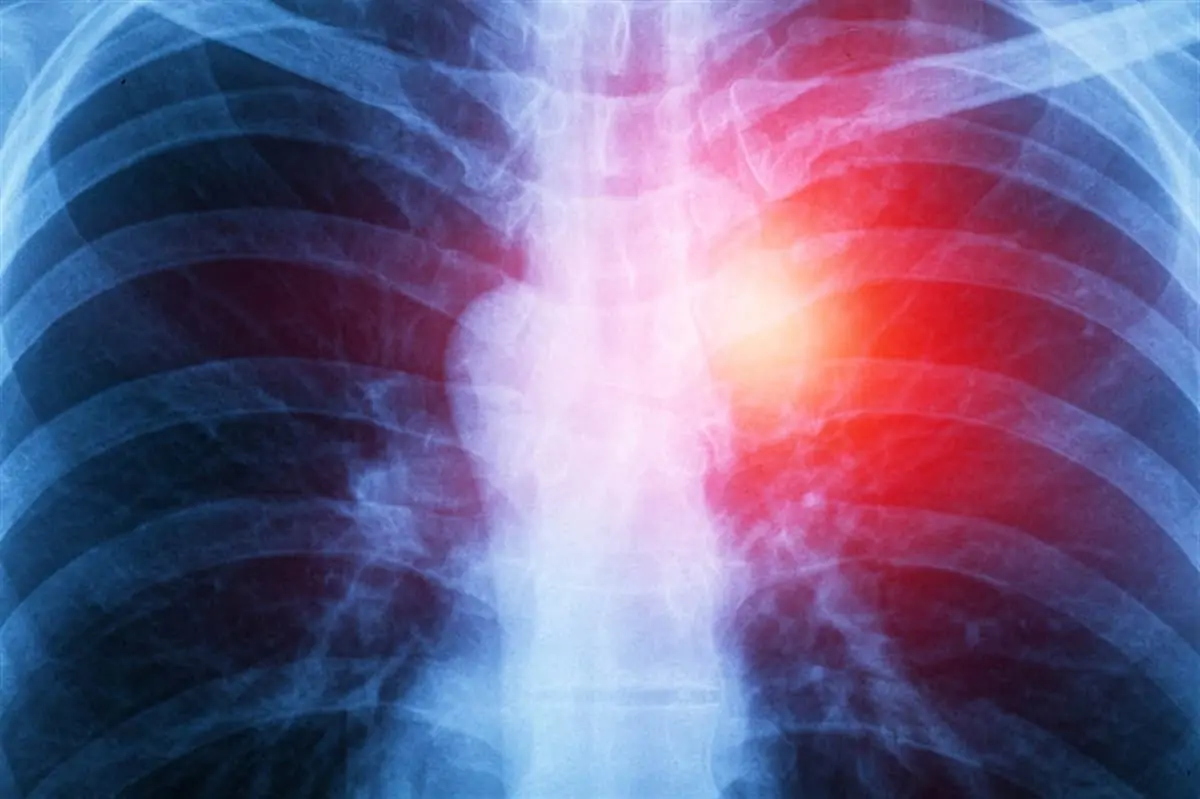

Mezotelyoma, akciğer zarında (pleura), karın zarında (periton), kalp zarında (perikard), ya da testis zarında (tunica vaginalis) gelişebilen nadir fakat agresif bir kanser türüdür. Mezotelyoma en sık akciğer zarında görülür ve bu türüne “plevral mezotelyoma” denir.

Mezotelyoma, mezotelyal hücrelerden kaynaklanan nadir ve agresif bir kanser türüdür. Mezotelyal hücreler, akciğerler (pleura), karın boşluğu (periton), kalp (perikard) ve testisler (tunica vaginalis) gibi vücut boşluklarını ve iç organları çevreleyen ince bir zar olan mezotelyumda bulunur. Mezotelyoma en sık plevral mezotelyoma olarak adlandırılan akciğer zarında meydana gelir. Ayrıca, 4 adet türü vardır. Bunlar;

- Plevral Mezotelyoma: Akciğer zarında (pleura) gelişir. En yaygın mezotelyoma türüdür.